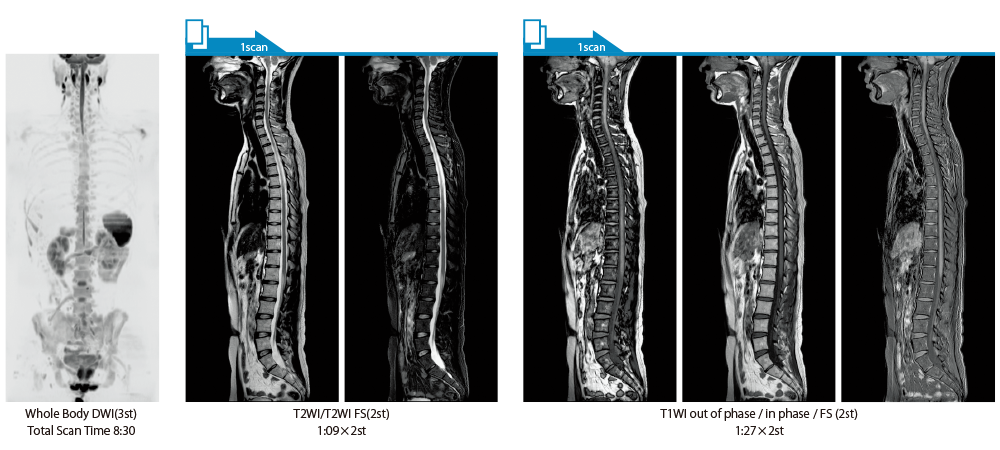

IP-RAPID×DLR PlusはVolumeScanやRadialScan、HalfScanといった基本撮像に加え、MultiContrastScanのFatSepやDWIなど多くの撮像法でお使いいただけます。広範囲DWIやWhole Spine撮像など時間のかかるWide Scanにも併用でき、多くの部位で従来よりも詳細な情報を得ることができます。

IP-RAPID×DLR Plusによって呼吸同期計測や横隔膜同期計測など時間のかかる検査を短くできます。さらに時間を短くし、息止めによる検査に変更することもでき、患者さまの状況に合わせて検査をお選びいただけます。選択肢が増えるので、検査の幅が広がります。